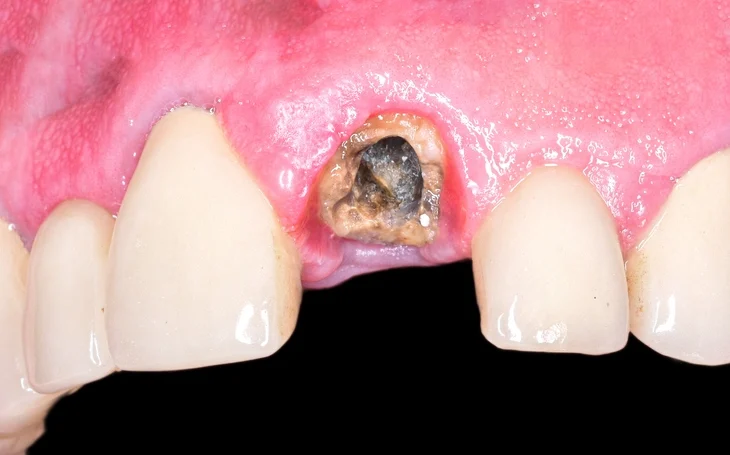

Clinical Examination

The clinician should evaluate:

- Visibility of the root

- Mobility

- Surrounding soft tissue condition

- Presence of infection or sinus tract

- Proximity to adjacent teeth

Palpation and gentle probing can provide valuable information regarding accessibility.